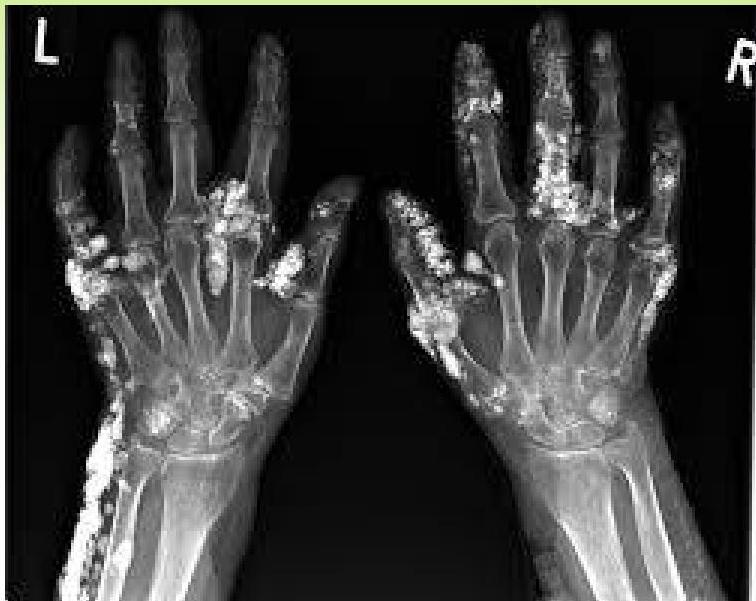

- Juvenile cases may develop calcinosis.